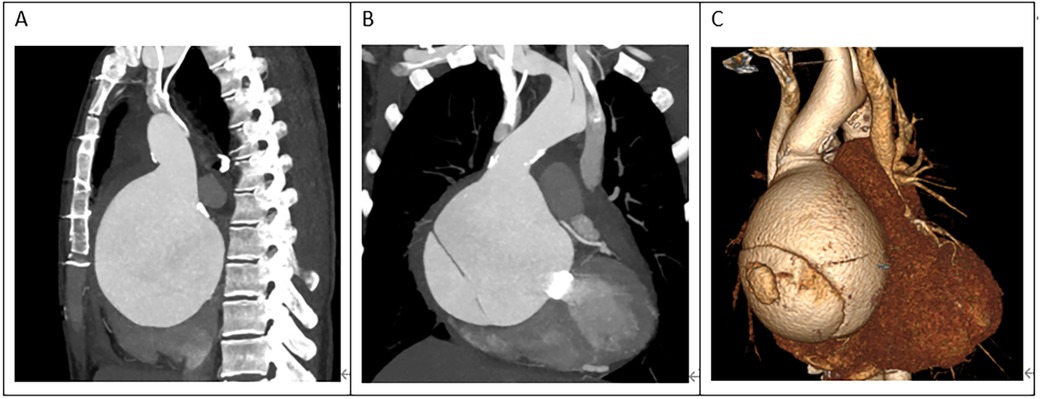

Figure 2

(A) The ascending aortic aneurysm was extremely large, occupying almost the entire mediastinum. (B,C) The heart was severely compressed.

A 45-year-old female patient, with a height of 155 cm and a low weight of 42 kg, was admitted to the hospital due to severe chest and back pain that had persisted for 9 h. The patient had undergone mechanical aortic valve replacement and aortic arch coarctation repair at our hospital 20 years earlier (the two operations were performed concomitantly). She had been taking warfarin for long time. She rarely received follow-up after surgery. Upon admission, the patient exhibited significant pain symptoms, accompanied by chest tightness, shortness of breath, and difficulty breathing; however, her vital signs were relatively stable, with a heart rate of 90–100 beats per minute. The physical examination revealed obvious surgical scars on the chest and left side of the thorax. Mechanical valve opening and closing sounds could be heard in the precordial area, along with a 3/6 grade systolic murmur. The electrocardiogram showed sinus rhythm, regular rhythm, and complete right bundle branch block. Echocardiography revealed a giant ascending aortic dissection aneurysm. The mean pressure gradient across the original mechanical aortic valve was 30 mmHg, with a peak gradient of 56 mmHg. The left ventricular diameter was 40 mm, the left atrial diameter was 19 mm, and the left ventricular ejection fraction (LVEF) was 70%. The enhanced computed tomography angiography (CTA) scan supported the presence of a giant ascending aortic dissecting aneurysm, with the largest cross-sectional area measuring approximately 101.3 × 85.2 mm (Figure 1). Contrast medium was observed to leak from the false lumen (Figure 1). The patient was slender, and the aneurysm occupied almost the entire anterior and posterior mediastinum (Figure 2A), severely compressing the heart (Figures 2B,C).